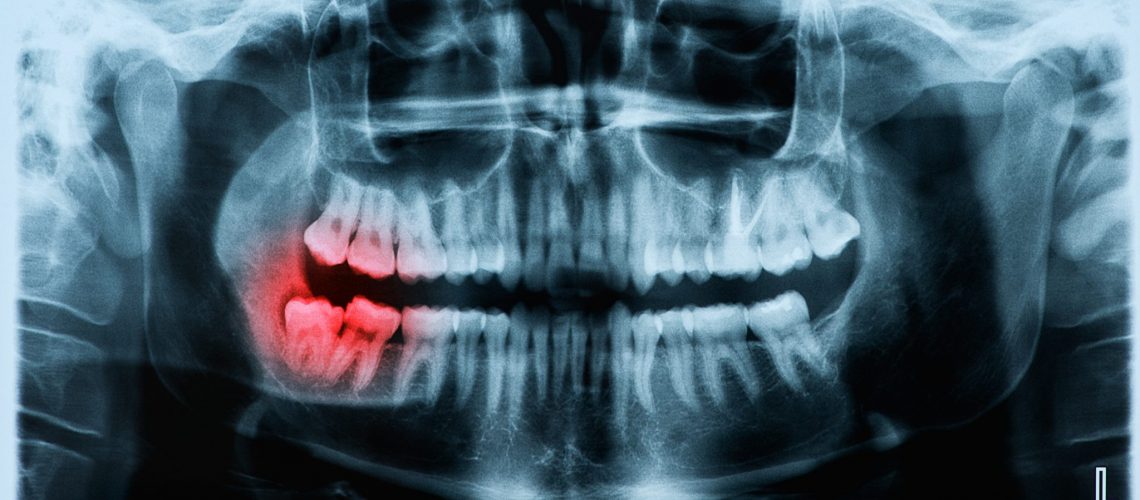

علت ورم صورت بعد از ایمپلنت

آیا بعد از جراحی ایمپلنت صورت ورم میکند؟ یکی از عوارض ایمپلنت دندان ایجاد ورم بعد از انجام کاشت انواع ایمپلنت دندان است. ورم بعد از ایمپلنت دندان می تواند به دلایل متعددی اتفاق بیافتد. در ادامه، به چندین عامل کلیدی که ممکن است علت ورم بعد از ایمپلنت دندان باشد، پرداخته ایم:

- واکنش التهابی: ورم بعد از ایمپلنت دندان ممکن است ناشی از واکنش التهابی باشد که در پاسخ به جراحی ایمپلنت رخ می دهد. بدن به عنوان یک واکنش به جسم خارجی اقدام به فعال سازی سیستم ایمنی می کند و به اطراف ایمپلنت مواد التهابی ارسال می کند. این واکنش ها ممکن است باعث تورم، قرمزی، درد و حساسیت در محل ایمپلنت شوند.

- عفونت: یک عامل مهم دیگر که می تواند منجر به ورم شود، بروز علائم عفونت ایمپلنت است. اگر عفونت در محل ایمپلنت رخ دهد، به عنوان پاسخ به میکروب ها و باکتری ها، بدن ممکن است با واکنش های التهابی شدید و ورم روبرو شود.

- تنش مکانیکی: نصب ایمپلنت دندان ممکن است باعث تنش مکانیکی در بافت های اطراف شده و واکنش التهابی را به دنبال داشته باشد. تنش های ناشی از فشارها یا حتی خطا در اندازه گیری ایمپلنت می توانند منجر به ورم شوند.

- نقص جراحی: اگر جراحی ایمپلنت دندان به نحو صحیح انجام نشود یا مشکلاتی در فرآیند بهبود و ترمیم پس از جراحی وجود داشته باشد، این موارد می توانند منجر به ورم شوند.

- حساسیت به مواد ایمپلنت: موادی که در ایمپلنت دندان استفاده می شوند، ممکن است برخی افراد دارای حساسیت به آن ها باشند. این حساسیت می تواند منجر به واکنش های التهابی و در نتیجه ورم شود.